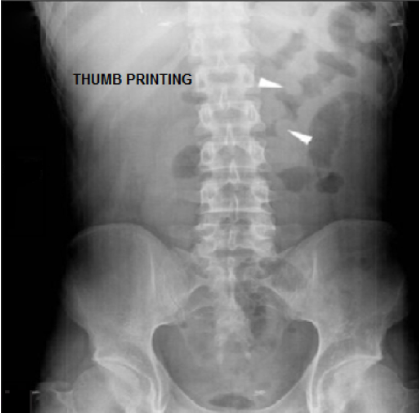

Thumbprinting sign is suggestive of _____

The thumbprinting sign is seen in both _____ colitis and _____ colitis.